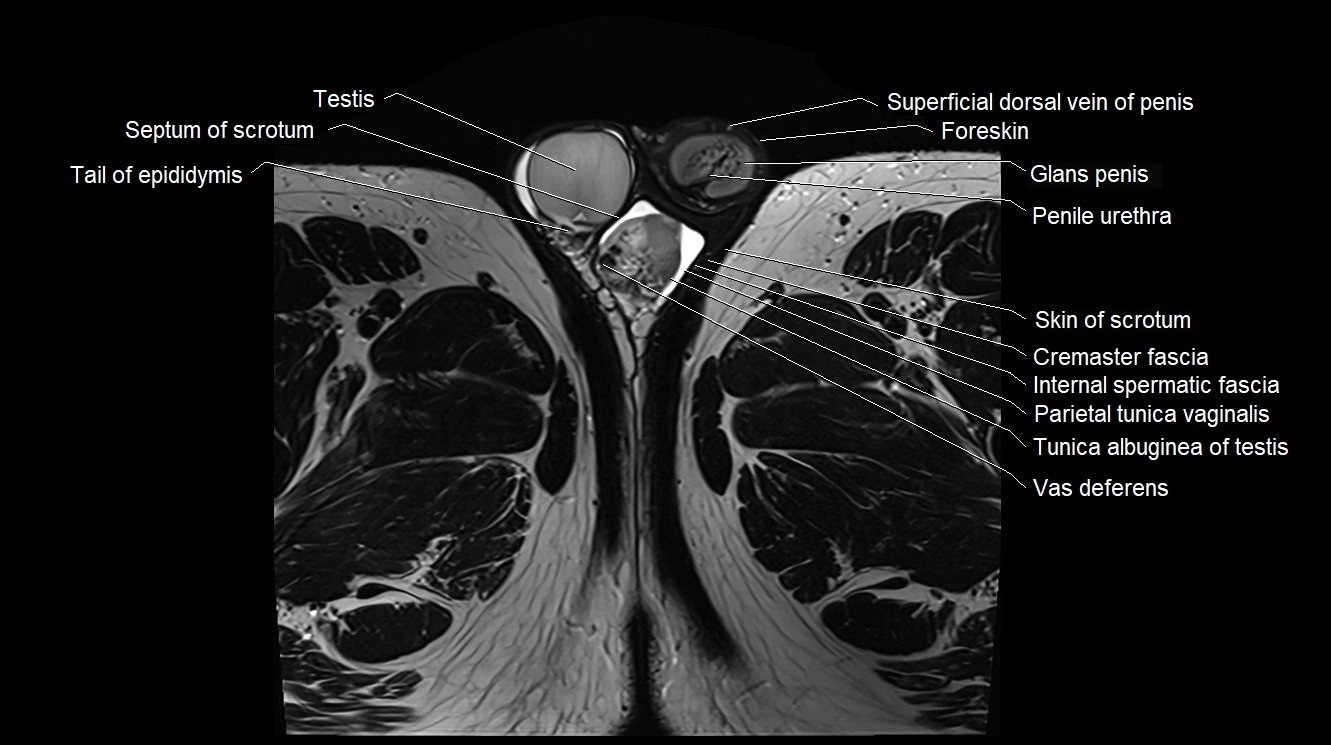

- Cremaster fascia

- Cremaster muscle

- External spermatic fascia

- Foreskin

- Glans penis

- Internal spermatic fascia

- Parietal tunica vaginalis

- Penile urethra

- Septum of scrotum

- Skin of scrotum

- Tail of epididymis

- Testis

- Tunica albuginea of testis

- Vas deferens

- Visceral tunica vaginalis